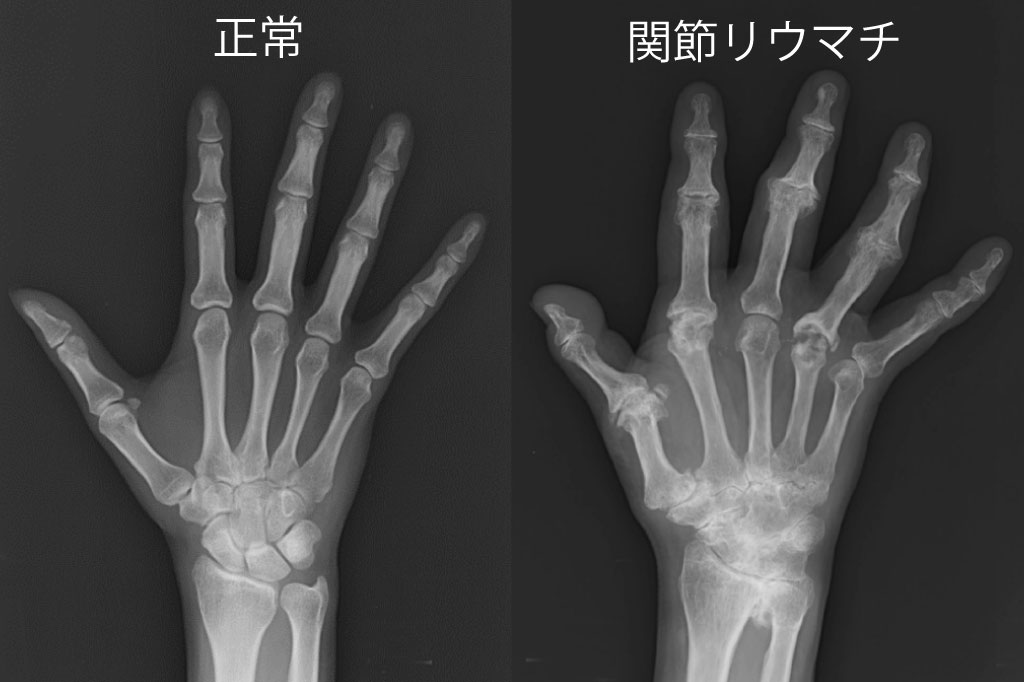

関節レントゲン検査

骨や軟骨の破壊の有無や関節の変形を確認します。レントゲンには炎症は映らず、関節炎の有無は判断できません。

発症して間もない早期の関節リウマチや、症状の軽い軽症の関節リウマチでは、レントゲンで明らかな異常を認めないこともしばしばあります。